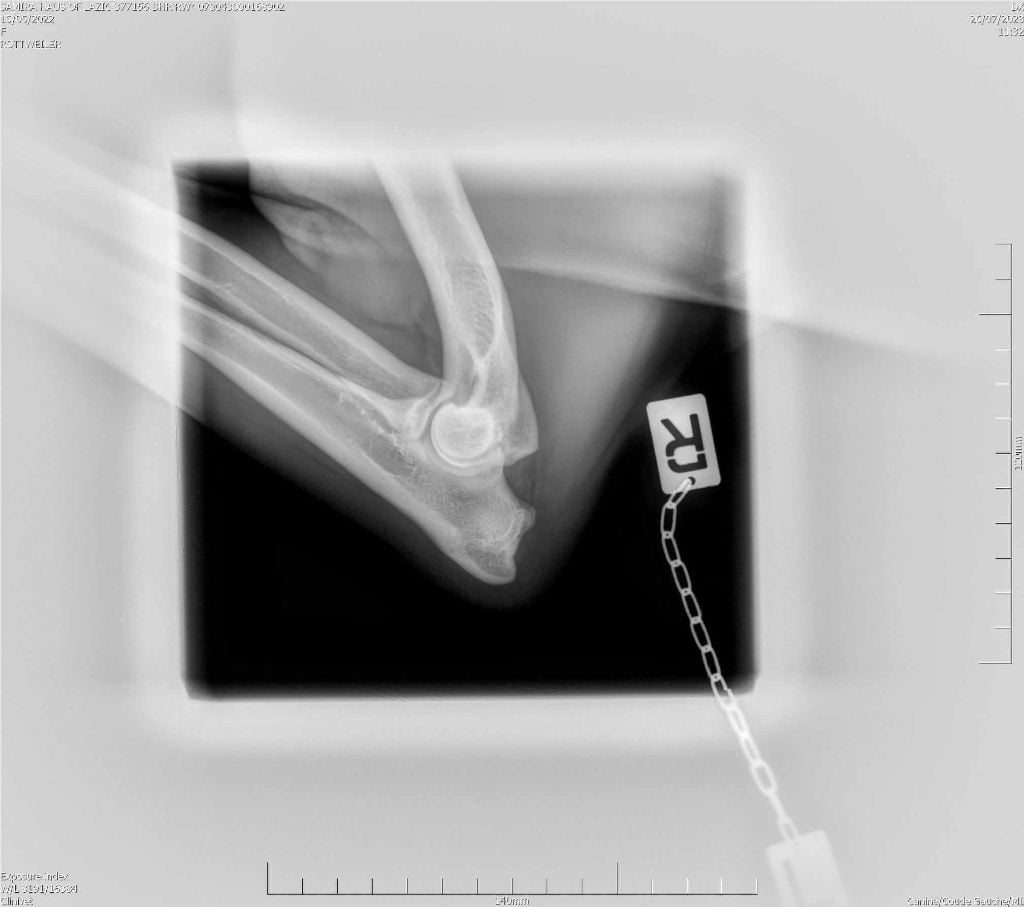

RADIO COUDE OFFICIELLE

COUDE SUITE

ADN : FAIT DYSPLASIE COUDES : ED0 DYSPLASIE HANCHES : HDA JLPP : CLEAR |